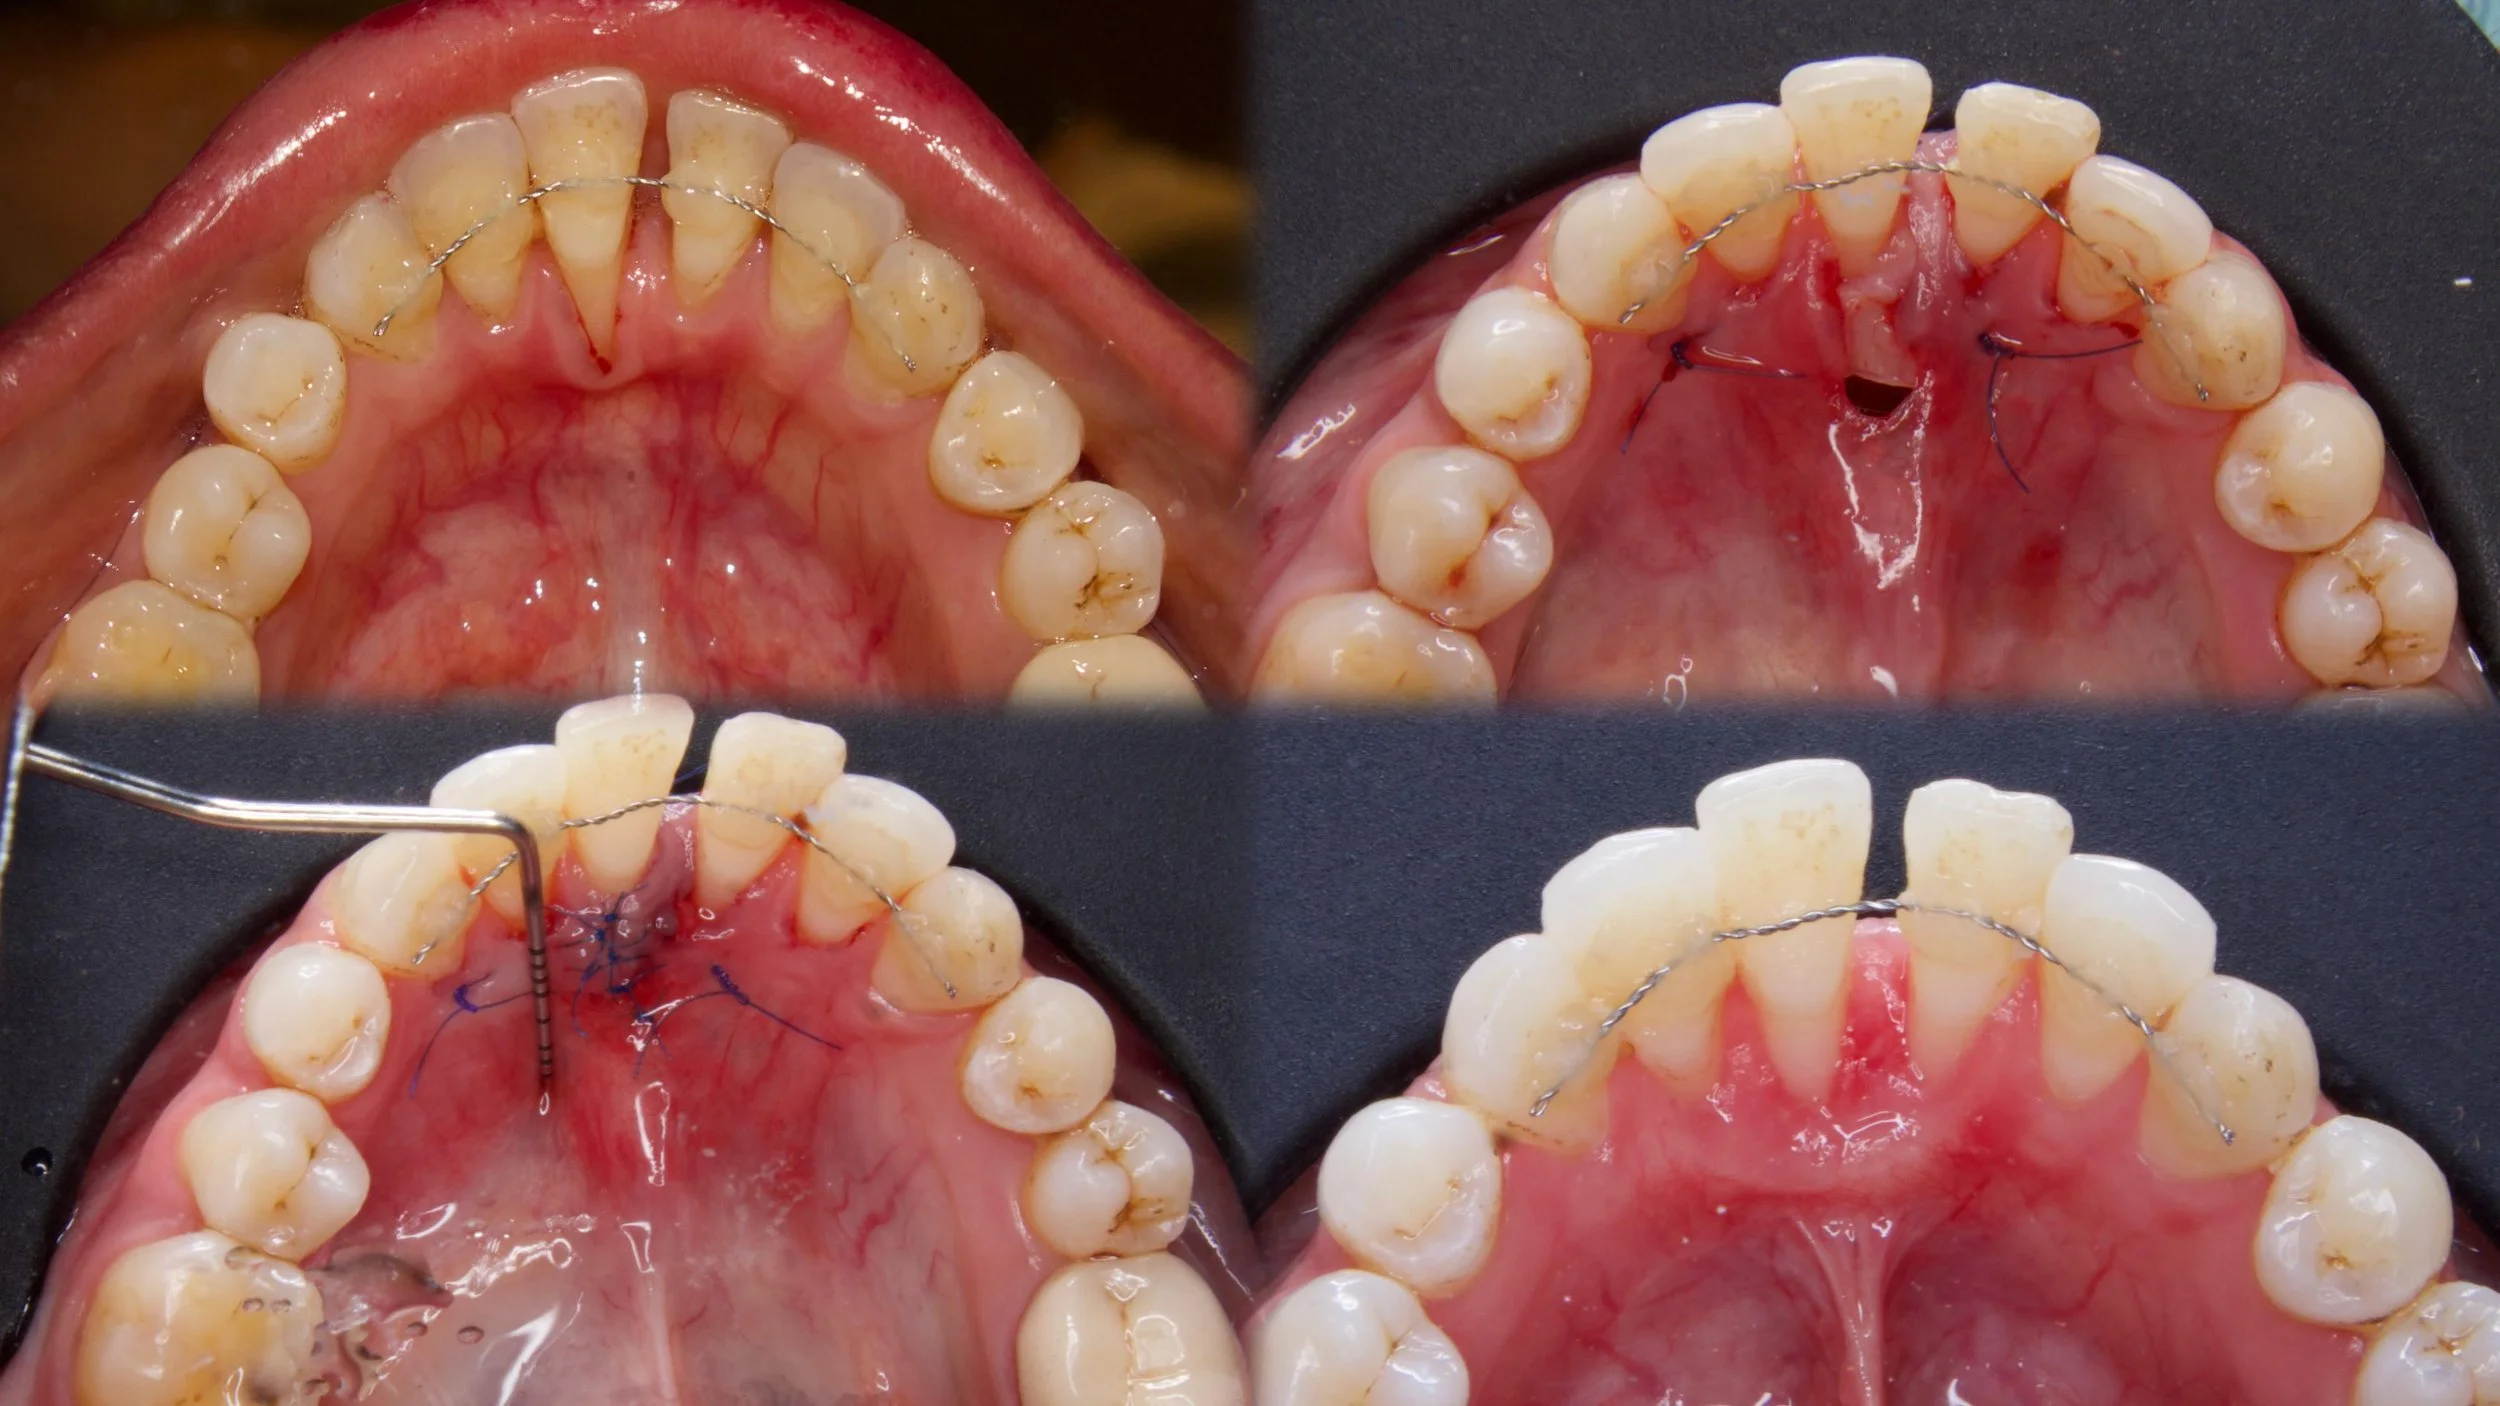

Root coverage with Tunelling and coronally advanced flap

Case done by Dr NIvedha, III year PG